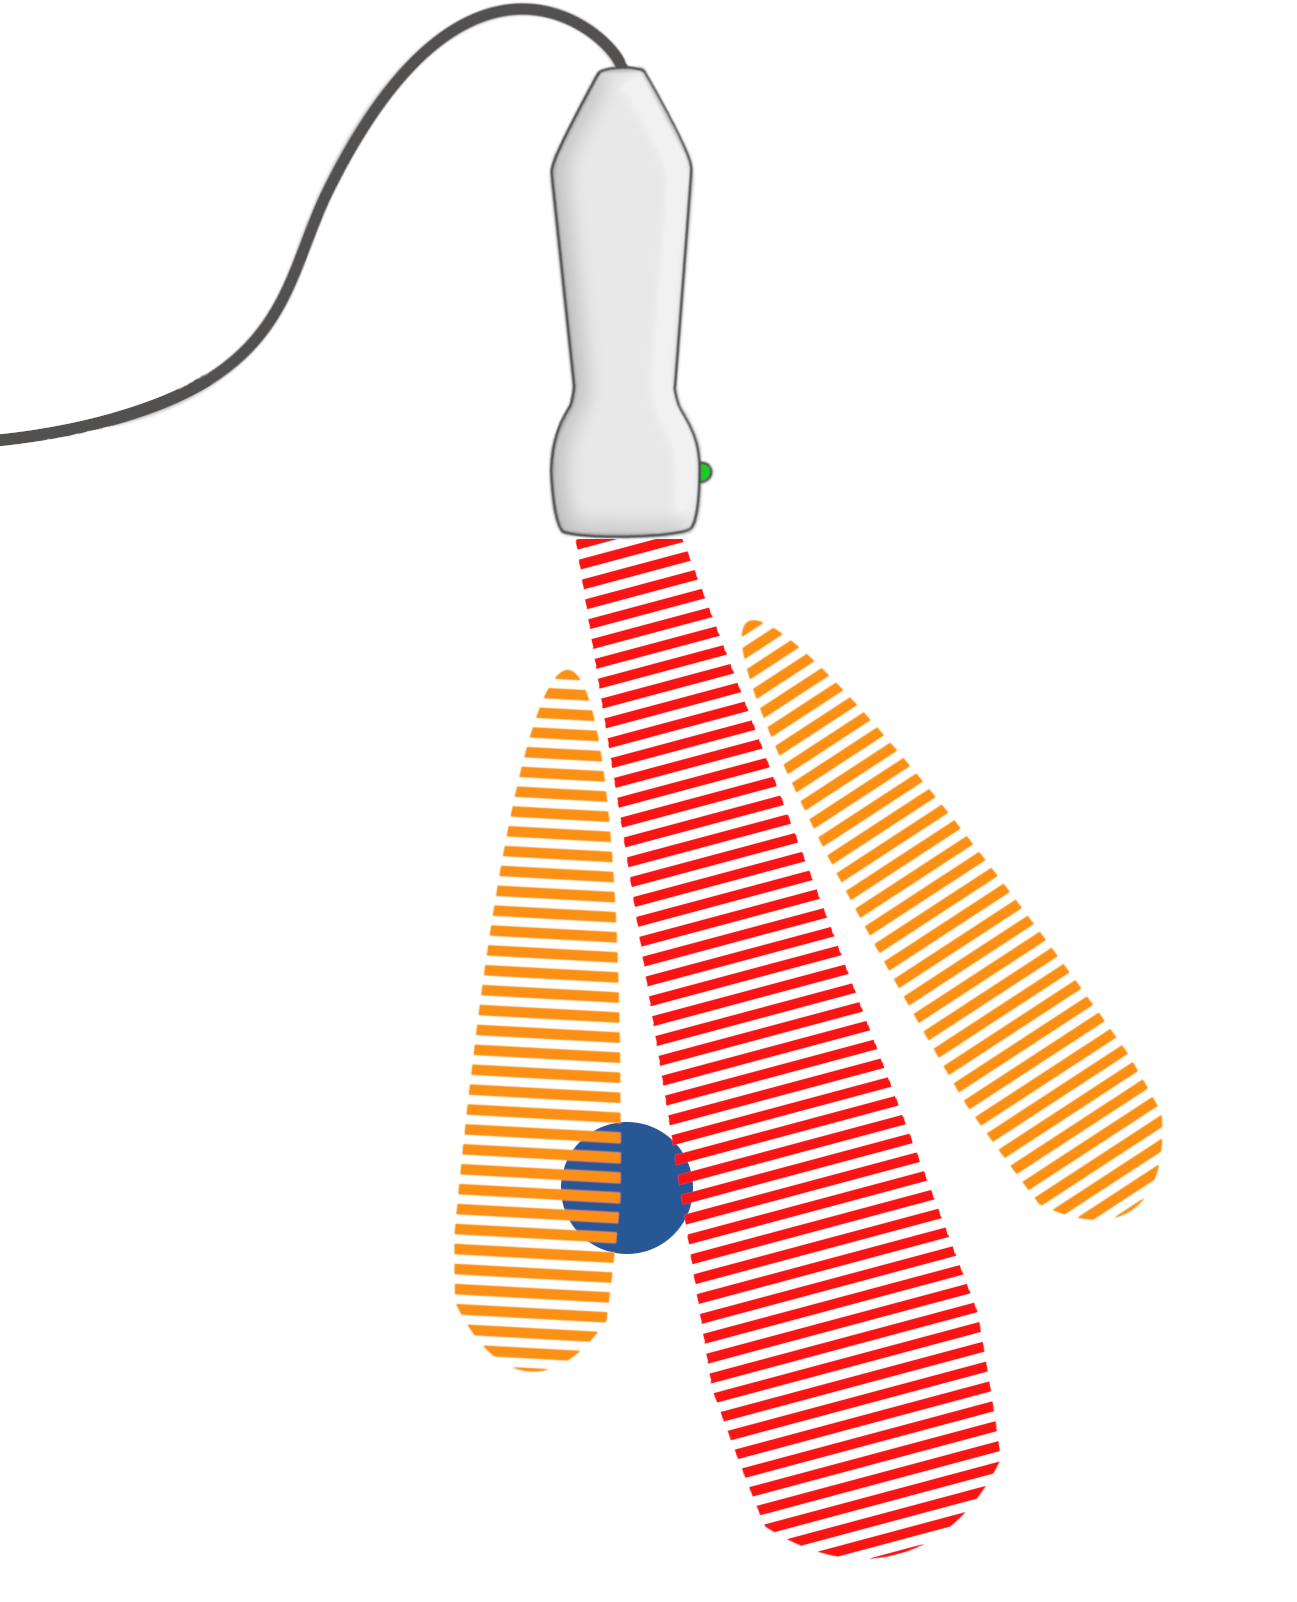

Nebenkeulen-Artefakte

Brechungsartefakte Brechungsartefakte Brechungsartefakte Brechungsartefakte

Größte Teil der vom Ultraschall erzeugten Energie ist in der Mitte konzentriert. Geringere Mengen der emittierten Energie wird zu den Seiten gelenkt und bilden dort sog. Nebenkeulen. Deren Energie verteilen sich normalerweise im Gewebe, ohne auffällige Echos zu erzeugen. Durch sich im Strahlengang der Seitenkeulen befindliche starke Reflektoren (z. B. Prothesenmaterial), können deren Reflexionen als vom zentralen Strahl stammend interpretiert werden. Neben dem eigentlichen Bild entsteht ein lineares, bogenförmiges Artefakt.